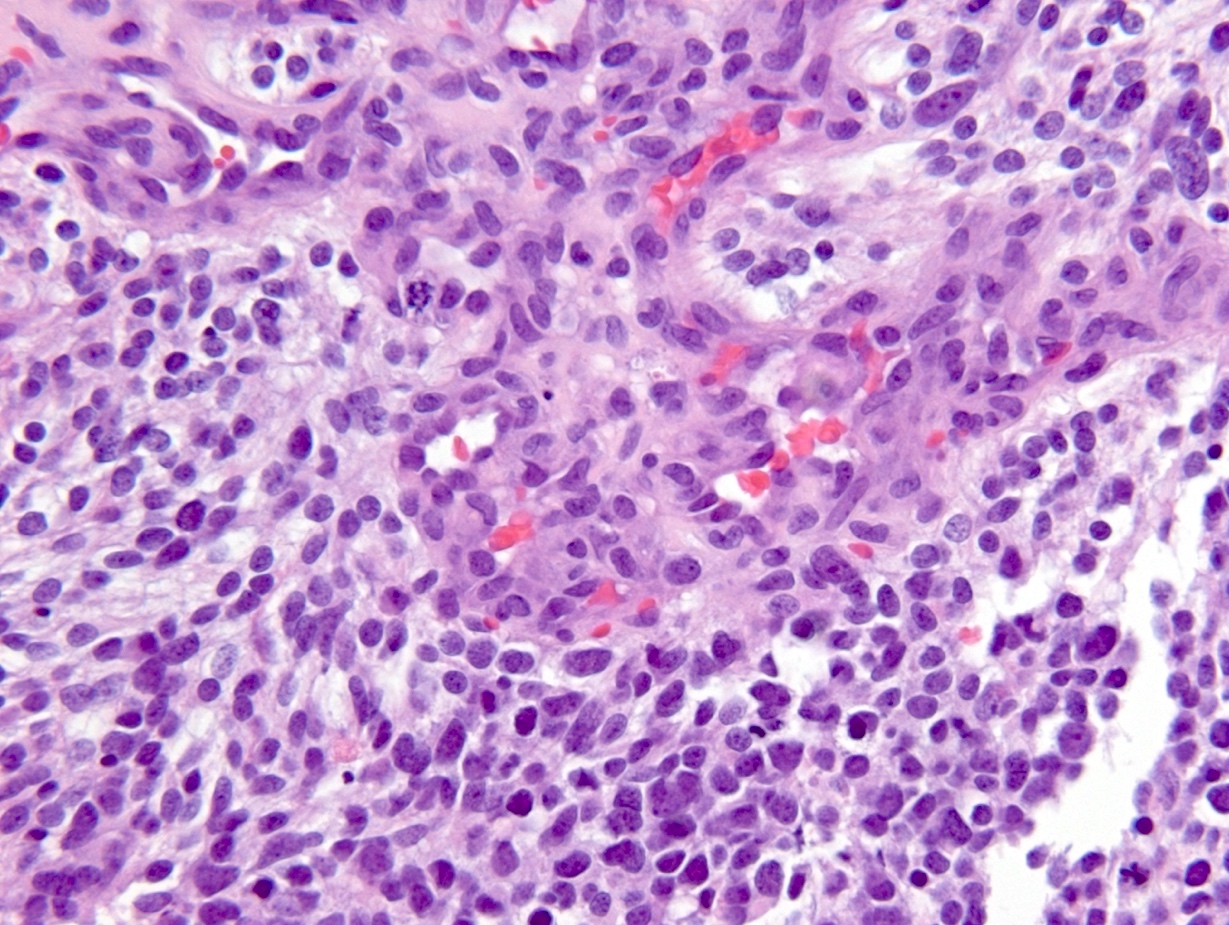

Microscopic (histologic) description

- Diffusely infiltrating tumor cells with oval to elongated astrocytic nuclei and varying appearance of tumor cytoplasm and fibrillar glial processes (Acta Neuropathol 2015;129:789)

- At the periphery, tumor cells may infiltrate in a diffuse single cell pattern, often with entrapped neurons and axons

- Cellular morphology is variable, even within a single tumor

- Commonly there is a mix of cells with elongated nuclei and fine fibrillar processes, cells with eccentric nuclei and glassy eosinophilic cytoplasm (gemistocytes), larger pleomorphic cells and small cells with scant cytoplasm

- May show oligodendroglioma-like areas

- Myxoid background and microcyst formation may be present

- Variable mitotic activity, cellularity and nuclear atypia depending on CNS WHO grade

- In small biopsy specimens, the presence of 1 mitosis may be sufficient for a CNS WHO grade 3 diagnosis, while the presence of a few mitotic figures in a large resection would not be sufficient for grade 3 designation (Acta Neuropathol 2020;139:603)

- Presence of necrosis or microvascular proliferation would be consistent with a CNS WHO grade 4 designation

Microscopic (histologic) images

Contributed by Eman Abdelzaher, M.D., Ph.D., John DeWitt, M.D., Ph.D. and Meaghan Morris, M.D., Ph.D.

Which of the following is true about the entity in the figure above presenting in a 50 year old man?

B. If R132H IDH1 immunohistochemistry is positive, ATRX staining of tumor cells is expected to be lost. The image is consistent with an infiltrating astrocytoma with significant pleomorphism and mitotic activity. If R132H IDH1 immunohistochemistry is positive, as stated in answer B, the findings are then consistent with astrocytoma, IDH mutant, CNS WHO grade 3. Astrocytoma, IDH mutant tumors often show concurrent ATRX mutation, indicated by loss of staining in tumor cells with ATRX immunohistochemistry.